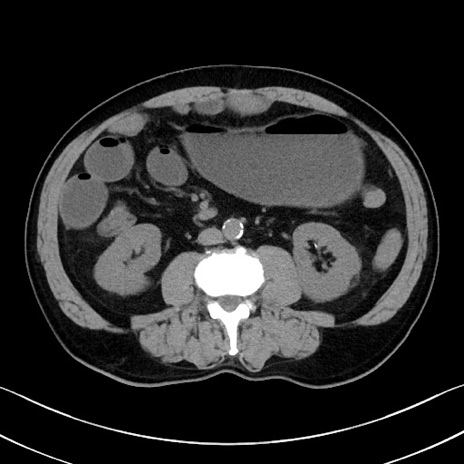

症例35(横断像)

【症例】70歳代 男性

【主訴】腹部膨満、嘔吐

【現病歴】昨日より腹部膨満感出現。本日増悪し、仙痛出現。嘔吐あり、受診。

【既往歴】糖尿病、胆摘後

【身体所見】BP 149/80mmHg、HR 74/min、BT 35.9℃、腹部:膨満、軟、圧痛なし。腸雑音減弱あり。上腹部正中切開瘢痕あり。

【データ】WBC 13500、CRP 1.72